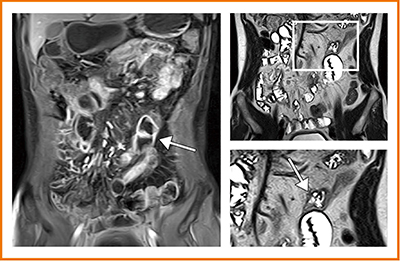

図2は,造影T1強調画像で近位回腸もしくは空腸に高い増強効果と小腸間膜のリンパ節肥大が認められた。T2強調画像で壁内浮腫を伴う病変が描出され,空腸潰瘍と診断した。同日に行われた小腸内視鏡で,空腸潰瘍が確認されている。

図2 空腸潰瘍